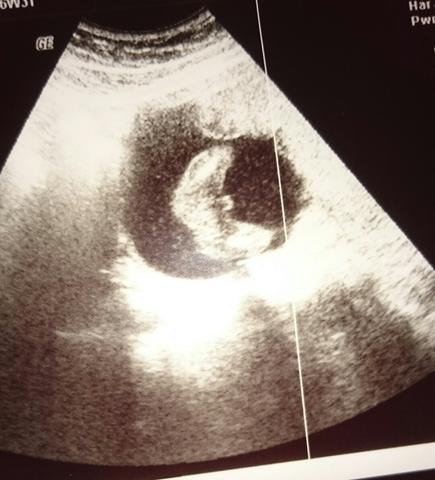

In der 15 SSW kann der Arzt im Ultraschall erkennen, ob die Schwangere ein Mädchen oder einen Jungen bekommt Beim männlichen Baby hat sich jetzt die Anlage für den Penis deutlich herausgebildet. Der Ultraschall zeigt in der 15 SSW das Geschlecht des Babys Vor allem Klitoris und Penis sind die beiden Unterscheidungsmerkmale, welche auf dem Ultraschallbild die Geschlechtsbestimmung ermöglichen Mit zunehmender Wochenanzahl, lässt sich die Bestimmung im Ultraschall immer sicherer durchführen. Im Ultraschall lässt sich das Geschlecht etwa ab SSW 15 erkennen Das aber auch nur, wenn sich das Baby in einer günstigen Position befindet und sich zeigen will Die Angaben sind jedoch nie zu 100% sicher Absolute Gewissheit werden sie erst nach der Geburt oder nach einer Chorionbiopsie oder Amniozentese haben.

Geschlecht ab SSW 15 sichtbar Im Ultraschall lässt sich das Geschlecht etwa ab SSW 15 erkennen Das aber auch nur, wenn sich das Baby in einer günstigen Position befindet und sich zeigen will Die Angaben sind jedoch nie zu 100% sicher Absolute Gewissheit werden sie erst nach der Geburt oder nach einer Chorionbiopsie oder Amniozentese haben. Was zeigt der Ultraschall in der 15 Woche?. Wir wussten in der 16 SSW dass es ein Junge wird und dabei blieb es auch Aber damit haben wir es schon sehr früh erfahren X xhappymom Themenersteller Benutzer Registriert seit Beiträge 22.

Ultraschall 32 SSW Hier sieht man, dass dieses Baby ein Junge ist Der kleine Penis ragt deutlich nach rechts ins Bild Wenn das Baby günstig liegt, kann man schon um die 14 SSW das Geschlecht erkennen Spätestens mit einem Ultraschallbild wie diesem ist dann aber klar, ob es ein Junge oder ein Mädchen wird. Im Ultraschall lässt sich das Geschlecht etwa ab SSW 15 erkennen Das aber auch nur, wenn sich das Baby in einer günstigen Position befindet und sich zeigen will Die Angaben sind jedoch nie zu 100% sicher Absolute Gewissheit werden sie erst nach der Geburt oder nach einer Chorionbiopsie oder Amniozentese haben. Mädchen oder Junge das Geschlecht Ihres Babys steht genetisch bereits ab der 3 SSW fest.